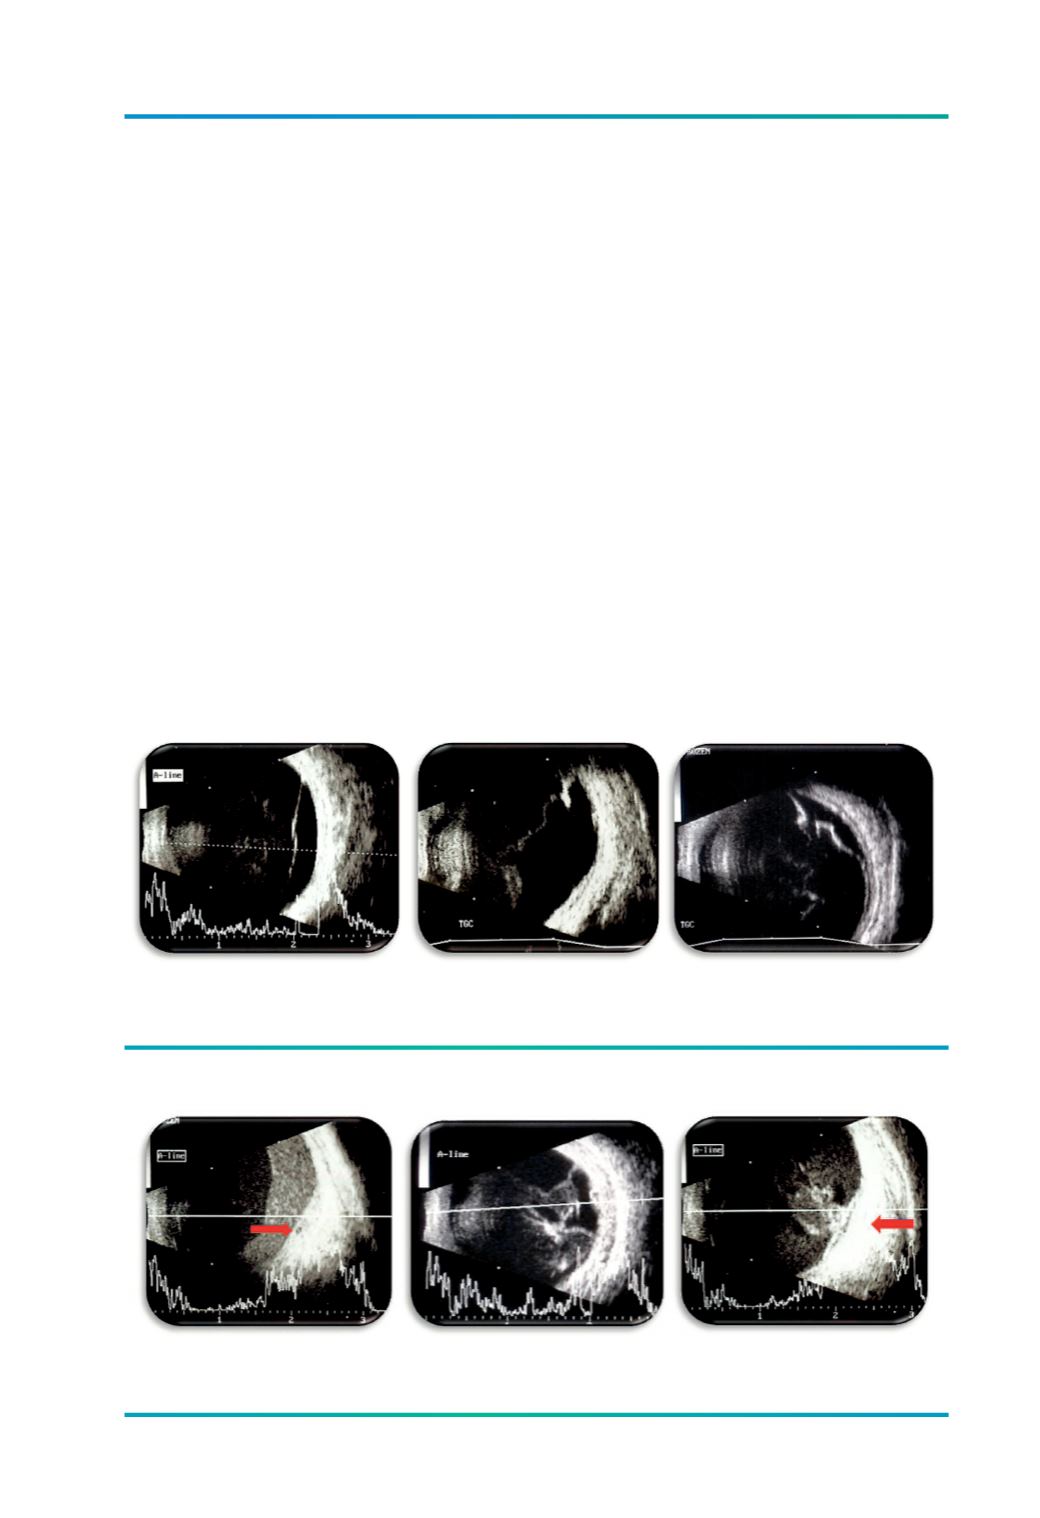

Figura 3.

Hemovítreo: A) HV com hifema posterior; B) HV organizado; C) HV com tracção retiniana.

O

hemovítreo

apresenta-se sob a forma de

múltiplos pontos brilhantes de baixa/média

reflectividade, móveis na cavidade vítrea. Na

presença de um DPV, o sangue pode per-

manecer entre a HP e a retina, mantendo-se

fluído e com tendência para formar um nível

posterior –

hifema posterior

(Figura 3 A). Em

hemorragias mais antigas e organizadas sur-

gem várias interfaces sob a forma de bandas

e membranas (Figura 3 B), que podem simular

um descolamento de retina ou corresponder a

um verdadeiro DR traccional (Figura 3 C).